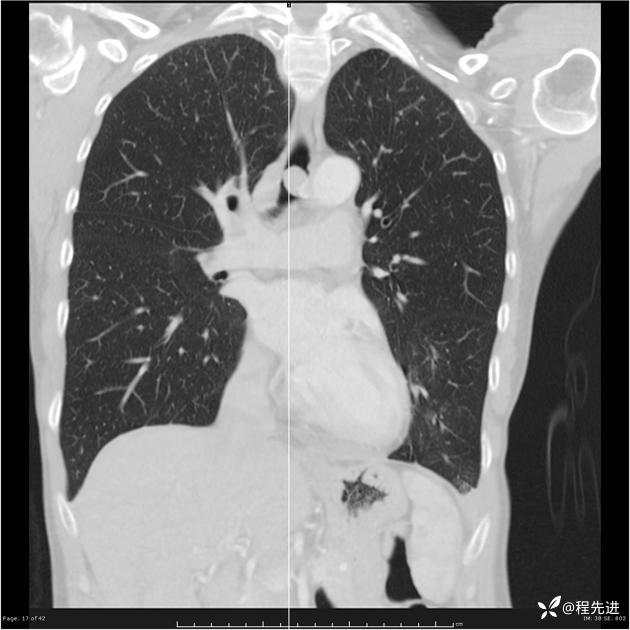

病例女,53岁,气管、左主支气管、下叶支气管内结节,乳头状瘤?期待你的精彩解读

女,53岁

乳头状瘤?